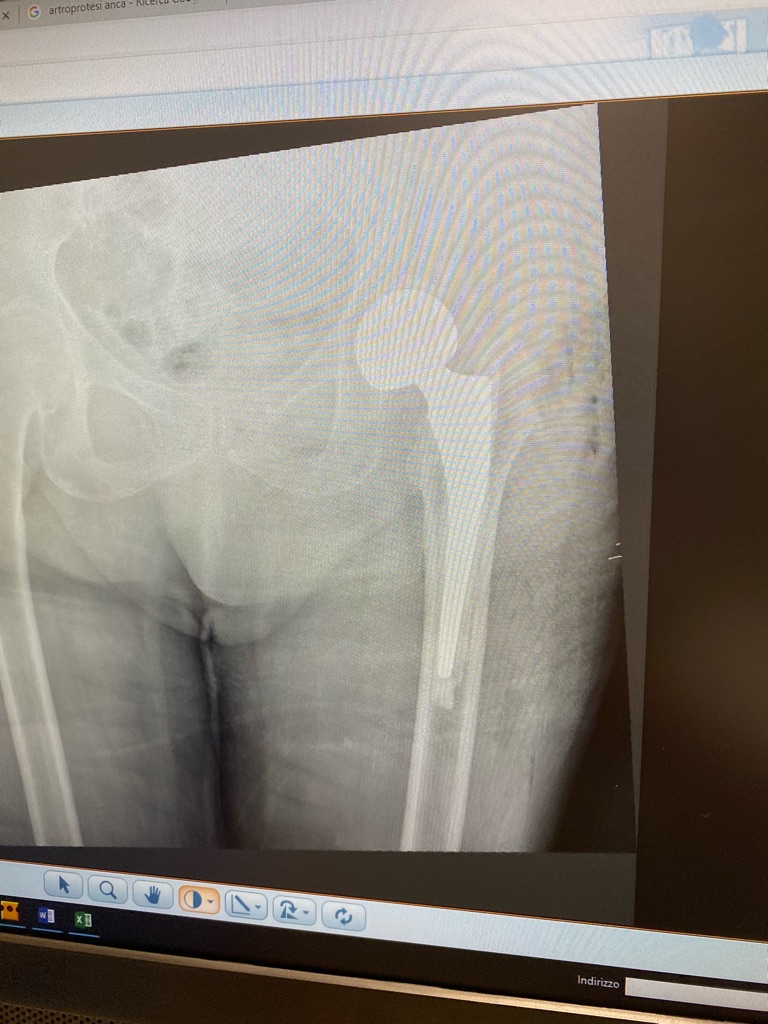

This is a Fitmore Hip Stem System and provides the patient an ability to move with increased normalcy following an injury to their hip. In this case the ball (femoral head) and the stem portion were fixed together, because the patient was a bit older with a more sedentary lifestyle.